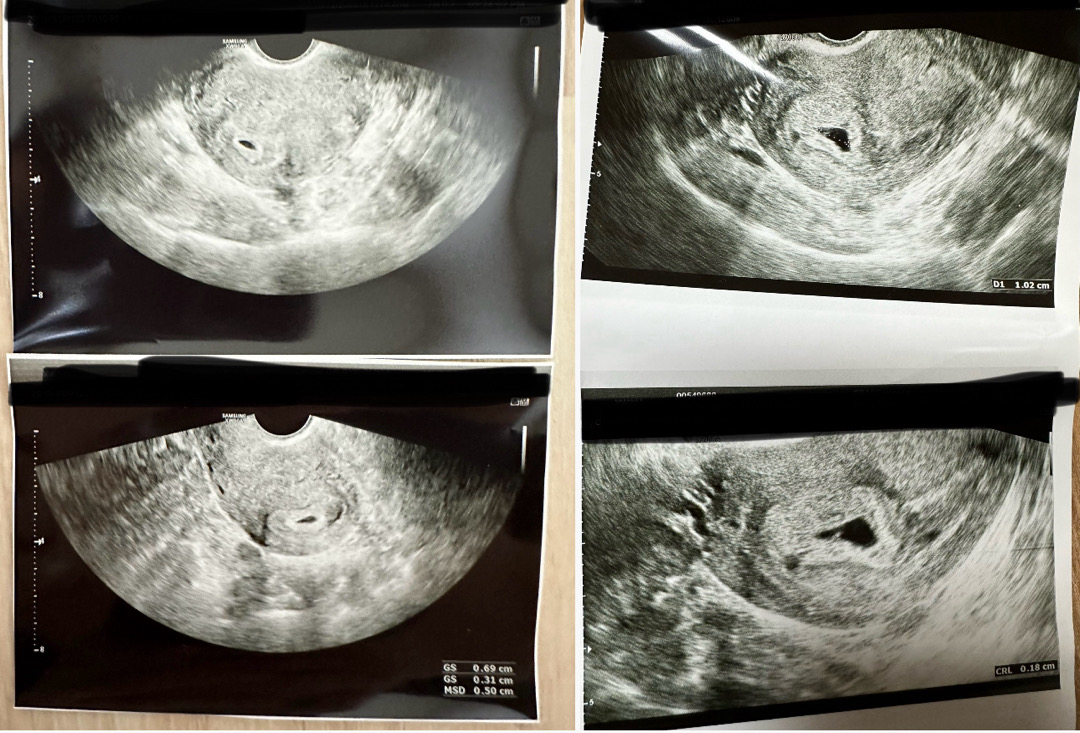

4주차에 아기집 보고, 7주진입해서 오늘 심장소리 들으러 다녀왔는데, 다른병원으로 갔거든요ㅠㅠ 4주차 초음파 사진에 비해.. 4-5일 정도 밖에 크지 않은거같다고.. 건강한 아기가 아닐수 있다고 하시네요ㅠ 심장소리도 못듣고, 다음주 수술 괜찮냐고 하셨어요ㅠ 왼쪽이 4주차 초음파ㅜ오른쪽이 오늘 초음파요ㅜㅜ 이대로 포기하는게 맞을까요..?🥲 속상한 글 안쓰길 바랬는데ㅠㅠㅠㅠ 넘 속상해서 주저리해봐요ㅠ

crl이 머리에서 엉덩이 길이..7주차엔 1cm정도래요. 토닥토닥...